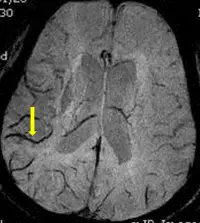

影像為腦部軸位 MRI,顯示大腦皮質及皮質下白質。最顯著的特徵是皮質靜脈(cortical veins)呈現極低訊號(markedly hypointense,即明顯黑色),於灰色腦實質背景中形成強烈對比,清晰勾勒出腦表面迂曲走行的皮質靜脈網路。黃色箭號所指為一條走行清晰、訊號極低的皮質靜脈。

此影像特徵——靜脈呈黑色、腦實質呈灰色、靜脈與腦組織間對比極佳——是 SWI 最具代表性的外觀:去氧血紅素(deoxyhemoglobin)為順磁性物質,造成局部磁場不均勻,使靜脈血中的訊號快速衰減(T2* 效應),導致靜脈在 SWI 上呈現深色(blooming effe